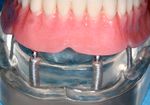

الجراحات التعويضية للتركيبات الغير ثابتة

Overdentures

Bar overdenture

A cast bar of metal is secured to the implants. The complete denture then attaches to the bar with semiprecision attachments allowing no movement of the denture.

Ball overdenture

Ball and socket type attachments can be placed on implants and dentures to prevent most movement.